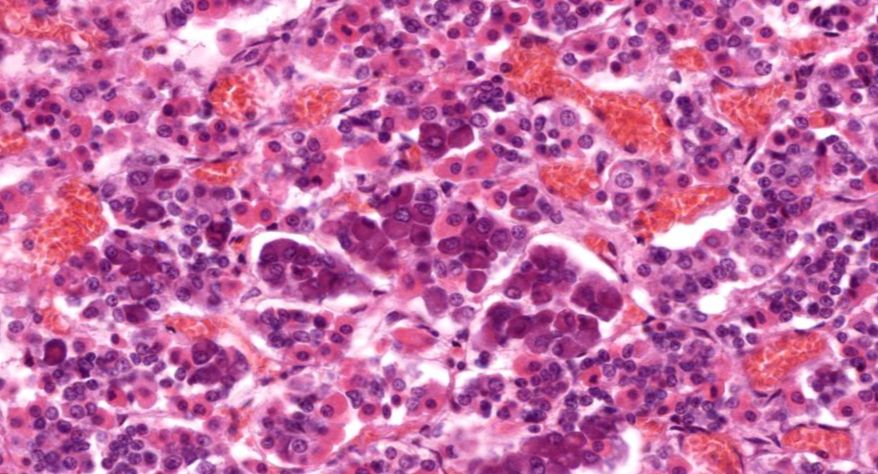

低倍镜观察:1. 被膜:由薄层结缔组织组成。2. 实质:由许多大小不等的滤泡构成。滤泡壁是单层立方上皮细胞,滤泡腔内充满粉红色匀质胶状物,滤泡之间的结缔组织内有丰富的血管。高倍镜观察:1. 滤泡:滤泡壁的单层滤泡上皮细胞一般呈低柱状或立方状,胞质着浅色,细胞核呈圆形。滤泡腔内充满了粉红色匀质胶质。2. 滤泡旁细胞:体积较大,呈圆形或椭圆形;细胞核较大,呈圆形,着色较浅,细胞质染色也较浅。细胞或嵌在滤泡壁上或成团分布于滤泡之间。3. 间质:由结缔组织组成。位于滤泡之间。其中含有丰富的毛细血管及三五成群的滤泡旁细胞。

2.滤泡

3.滤泡上皮细胞

4.胶质

5.滤泡旁细胞1

7.滤泡旁细胞2